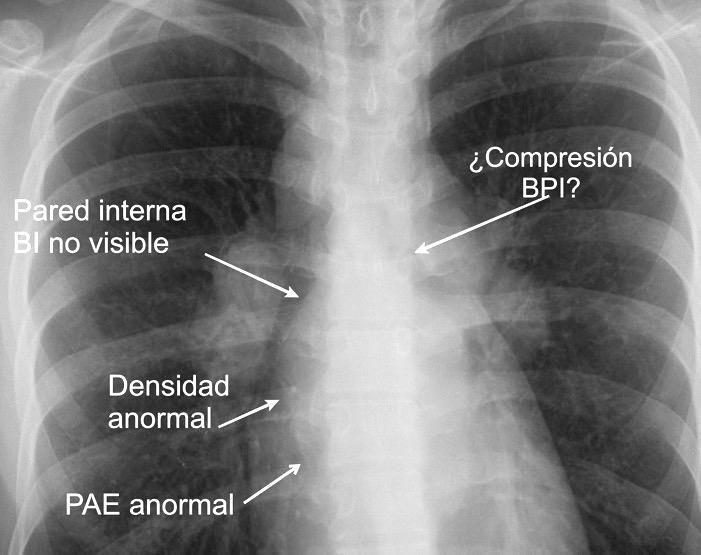

Normal

Espacio normal

Densidad baja uniforme del espacio. Pared interna de BPI-BI visible.

BPI sin alteraciones Ángulo carinal normal

Crecimiento AI

Ganglios Quiste broncogénico

Ganglios subcarinalesl Ángulo carinal normal

Sarcoidosis